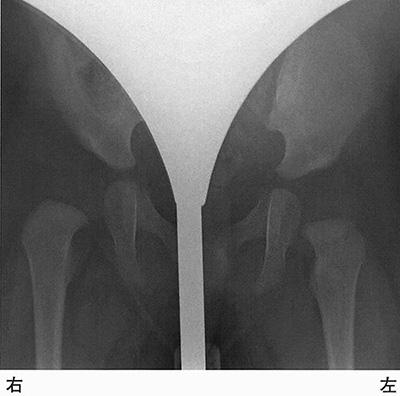

生後4か月の乳児。健診で股関節の異常を指摘された。来院時に右股関節の開排制限を認めたため、股関節のエックス線単純検査を行った。股関節の図を示す。臼蓋角はどれか。

生後4か月の乳児。健診で股関節の異常を指摘された。来院時に右股関節の開排制限を認めたため、股関節のエックス線単純検査を行った。行うべき対応として適切なのはどれか。